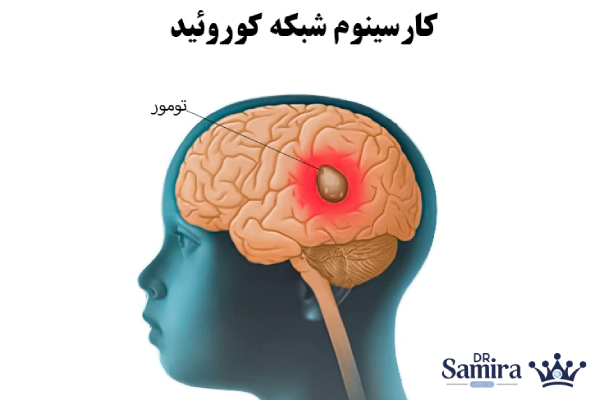

تفاوت پاپیلوما کوروئید پلکسوس با کارسینوم کورویید پلکسوس

پاپیلوما کوروئید پلکسوس یک تومور خوشخیم با رشد آهسته است، در حالی که کارسینوم کورویید پلکسوس یک تومور بدخیم و تهاجمی محسوب میشود. کارسینوم سرعت رشد بالاتری دارد، میتواند به سایر بخشهای مغز و نخاع گسترش یابد و نیازمند درمانهای ترکیبی مانند شیمیدرمانی و پرتودرمانی است. این تفاوتها باعث میشود رویکرد درمانی و پیشآگهی این دو بیماری کاملا متفاوت باشد.